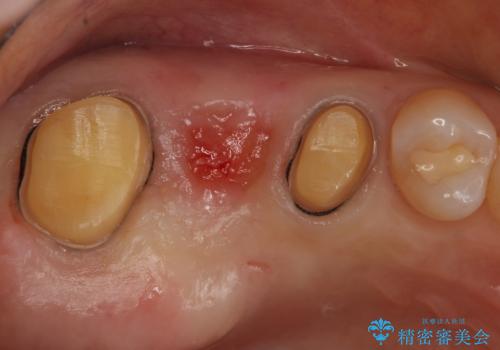

- 症状はないものの、検査の結果右上の奥歯が大きく割れていることが確認されたケースです。

無症状であったため放置していた結果、歯の周囲の骨が溶けてなくなっていました。

歯の深いところまで割れてしまっている場合は健康な状態での歯の保存ができないため抜歯の適応になります。

今回は抜歯後に骨の補填材を足し、適合の良いブリッジを装着していくこととなりました。